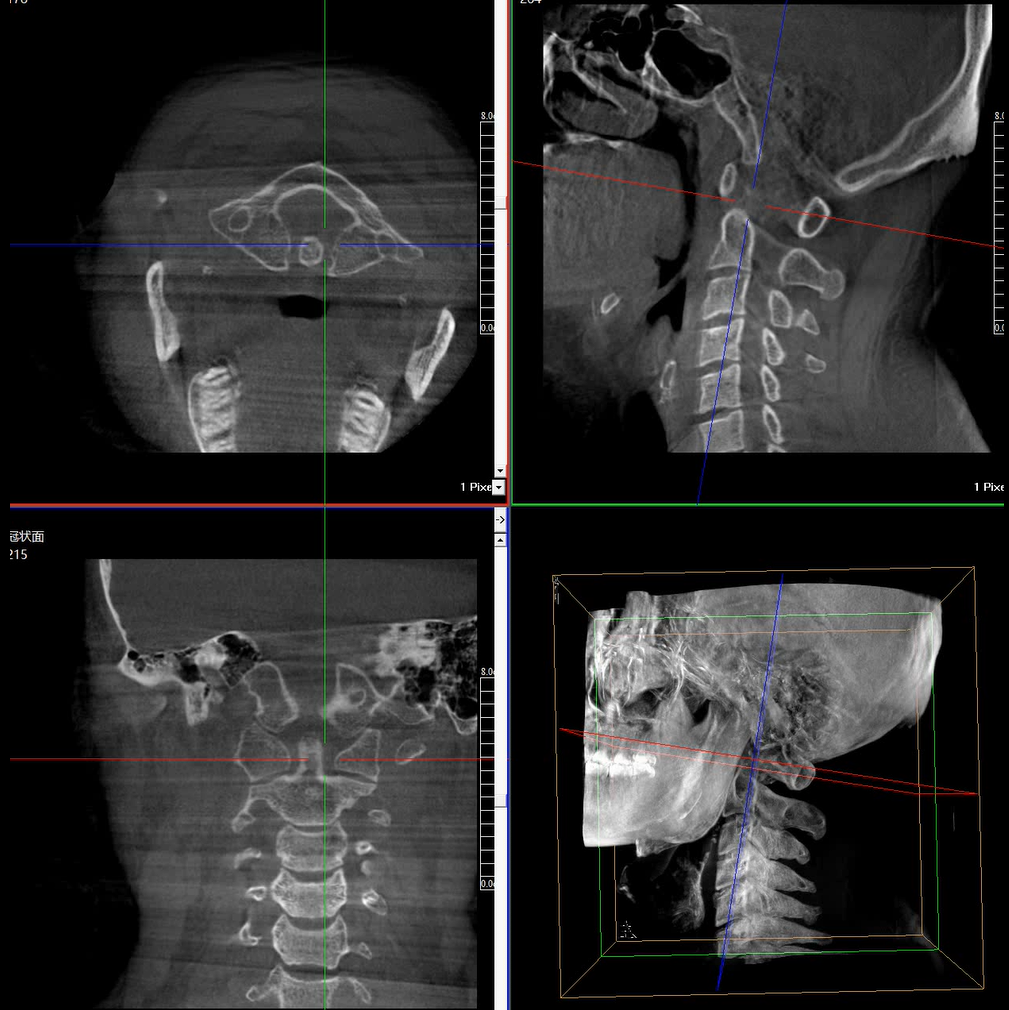

術(shù)中三維成像和橫斷面圖像提供多角度的手術(shù)診斷信息,輔助醫(yī)生進(jìn)行術(shù)中評(píng)估判斷,諸如骨折復(fù)位情況和內(nèi)植入螺釘?shù)某叽绾臀恢?,輔助手術(shù)更好地完成。

提供更大的術(shù)中三維成像視野,采集更多圖像信息,可一次拍全全段頸椎、全段腰椎、七節(jié)胸椎、雙側(cè)骶髂關(guān)節(jié)、股骨頭及單側(cè)盆骨。

在C臂掃描過程中,始終保持拍攝主體處于射線束的中心,避免了序列圖像采集過程中的橫縱方向運(yùn)動(dòng),減少相對(duì)運(yùn)動(dòng)造成的運(yùn)動(dòng)偽影。